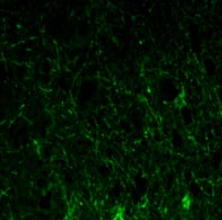

GFAP, a class-III intermediate filament, is a cell-specific marker that, during the development of the central nervous system, distinguishes astrocytes from other glial cells.Tissue specificity: Expressed in cells lacking fibronectin.ABCAM:It is heavily, and specifically, expressed in astrocytes and certain other astroglia in the central nervous system, in satellite cells in peripheral ganglia, and in non myelinating Schwann cells in peripheral nerves.In addition many types of brain tumor, presumably derived from astrocytic cells, heavily express GFAP. GFAP is also found in the lens epithelium, Kupffer cells of the liver, in some cells in salivary tumors and has been reported in erythrocytes.

IF/ICC    1/200 - 1/1000